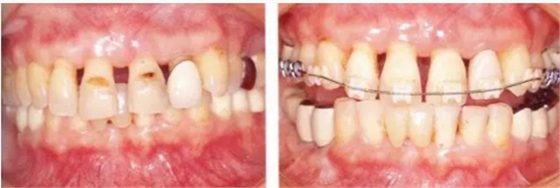

在正畸治療結束后仍然存在open contact的病例

▲圖15-1,2

在正畸??漆t(yī)生處接受了正畸治療,雖然上頜正畸治療已經(jīng)完成,但由于磨牙區(qū)的邊緣嵴不整齊而導致牙體之間存在空隙。要想在這個狀態(tài)下護理牙周組織以及咬合狀況是非常困難的。由此可見,在治療時,正畸專科醫(yī)生與全科口腔醫(yī)生保持目標一致是非常重要的。